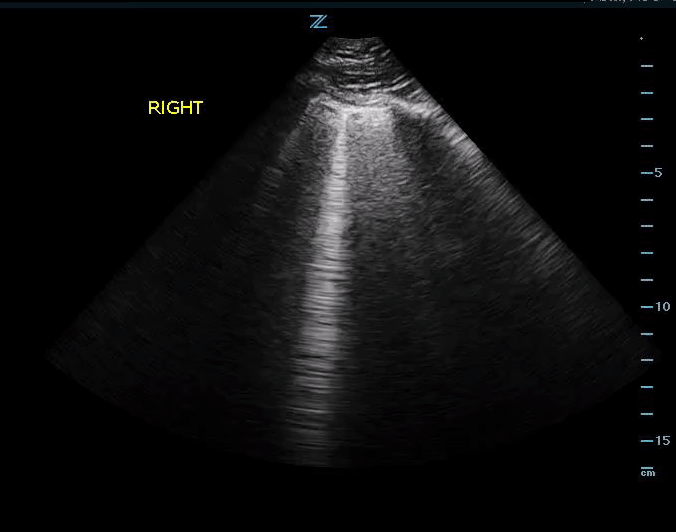

More B Lines….